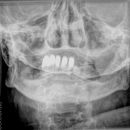

Wirbelsäule

Deckplatte LWK 2 ohne Hinterkante